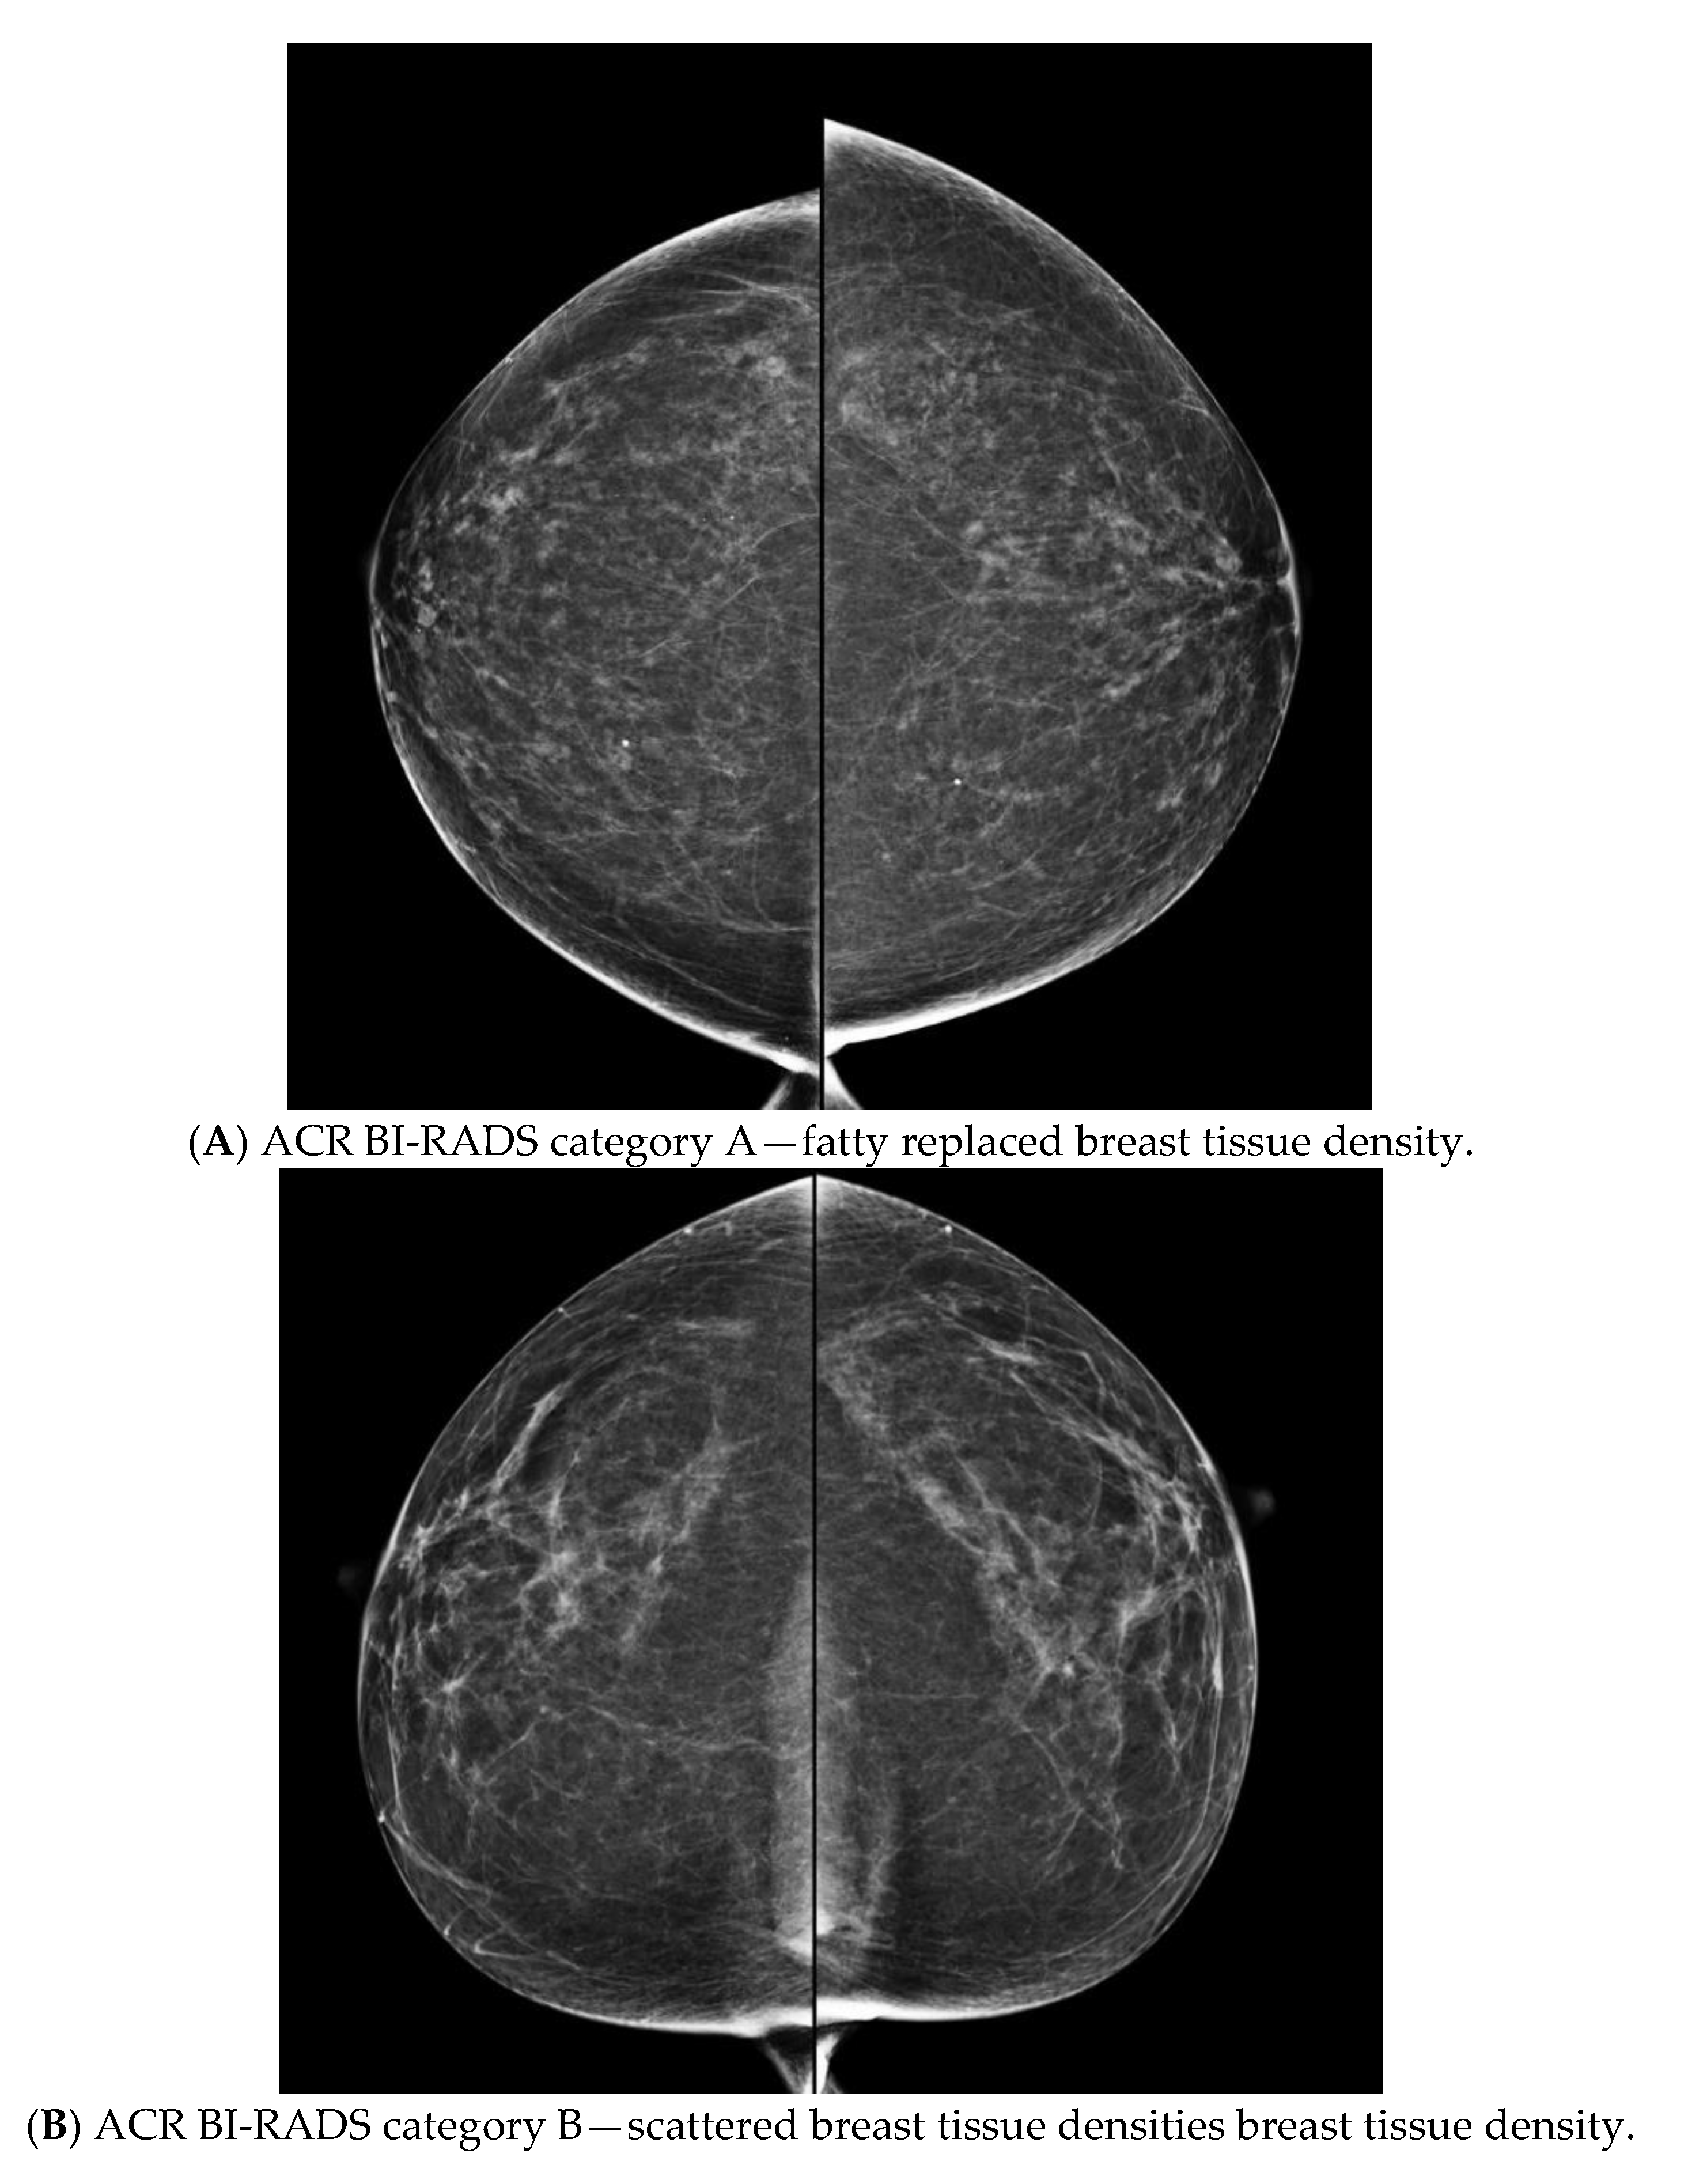

- Sickles, E.; D’Orsi, C.; Bassett, L.W. ACR BI-RADS® Mammography. In ACR BI-RADS® Atlas, Breast Imaging Reporting and Data System; American College of Radiology: Reston, VA, USA, 2013. [Google Scholar]

- American College of Radiology. ACR BI-RADS Atlas—Mammography, 4th ed.; American College of Radiology: Reston, VA, USA, 2003. [Google Scholar]